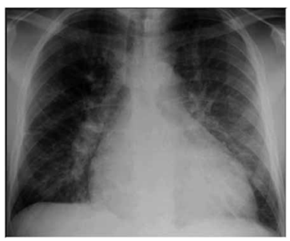

Paciente do sexo masculino, 57 anos de idade, acompanhado pela esposa, procurou serviço de urgência por dispneia aos pequenos esforços, edema de membros inferiores, diminuição do volume urinário, tosse seca associada a dispneia progressiva. Os sintomas se iniciaram há, aproximadamente, 6 meses, com dispneia seguida de edema. A dispneia, que era aos esforços moderados, rapidamente progrediu até estar presente no repouso. À ausculta pulmonar apresentou roncos e estertores em bases pulmonares. Ao raio X apresentou a radiografia a seguir:

(Arquivo pessoal, imagem usada com autorização)

Qual o provável diagnóstico de acordo com o caso clínico e com a imagem apresentados?